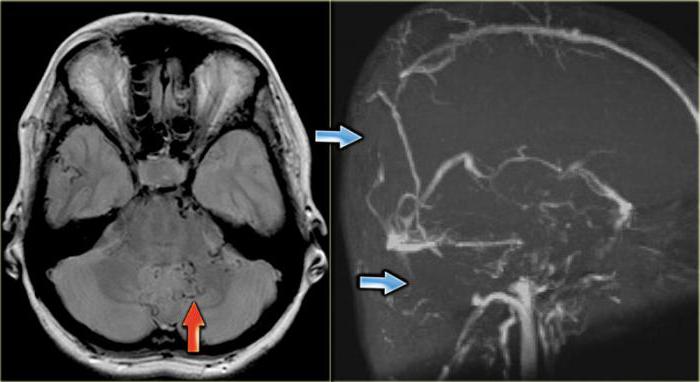

Как известно, синуситы подразделяются на несколько разновидностей. Наиболее распространённым считается воспаление гайморовой пазухи. Оно может быть как одно-, так и двухсторонним. Реже воспаление развивается в клиновидных (сфеноидит) и решётчатых пазухах (этмоидит). Также возможно инфицирование сразу всех перечисленных анатомических образований. Сочетанное воспаление пазух носа носит название пансинусит. Различить изменения на рентгенограмме удаётся не всегда. В этих случаях доктора рекомендуют выполнить МРТ пазух носа. Этот метод позволяет хорошо рассмотреть все ткани черепа. МРТ является диагностической процедурой, позволяющей послойно визуализировать органы и системы определённой анатомической области. На сегодняшний день данный метод считается одним из самых информативных способов выявления патологий. Компьютерная и магнитно-резонансная томография пазух носа позволяет увидеть изменения, которые нельзя рассмотреть никакими другими аппаратами для диагностики. Данные методы получили широкое применение во всех странах.

В некоторых случаях обыкновенной томографии недостаточно для диагностики. Тогда применяется МРТ с контрастированием. Наиболее часто встречающимся показанием для подобного обследования является подозрение на онкологические процессы в носовых пазухах или рядом с ними. В качестве контрастного вещества используется гадолиний. Его вводят в сосудистую систему. Контраст окрашивает артерии или вены исследуемой области, тем самым, улучшая визуализацию.

Только в случаях необходимости стоит назначать МРТ пазух носа. Что показывает данное обследование? Расшифровкой снимков занимает врач-рентгенолог или отоларинголог. По данным МРТ можно увидеть нарушение структуры тканей, тень от патологического образования и т. д. Благодаря данному методу диагностируют следующие патологии: